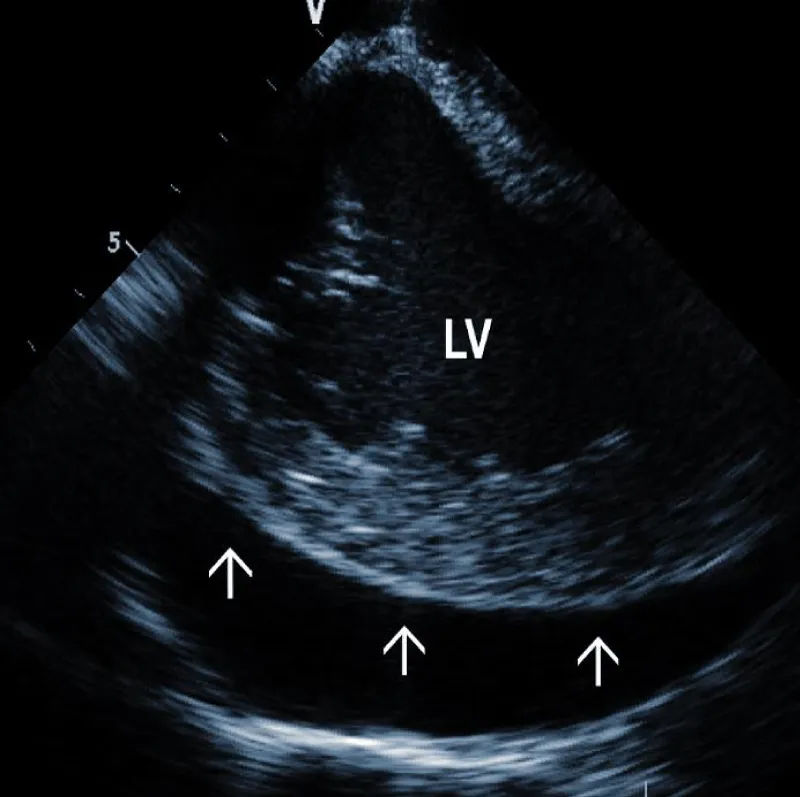

Pericardial effusion (hemopericardium): Intraproce-dural monitoring of pericardial effusion is one of the most important roles of ICE (Figure 5A). The incidence of significant pericardial effusion ranges in different studies between 0.4% - 3% [27-29]. Its immediate detection allows rapid decisions about further management. Catastrophic bleeding from the tear of the SVC may be stopped by the balloon inflation, allowing time for surgical repair. In less dramatic cases, pericardial drainage can be performed before any hemodynamic consequences occur. Our strategy is to drain every pericardial effusion that reaches more than 5 mm circumferentially. We typically use a kink-resistant 8F sheath (Arrow) to enable rapid exchange of the drainage catheter in case of blood clotting.

Figure 5A: Large separation (arrows) around the Left Ventricle (LV).

Some studies determined variables most closely associated with new-onset pericardial effusion during TLE [29]. These included three clinical factors (NYHA class III/IV, LVEF < 35%, renal impairment) and two factors related to the system itself (right-sided implant site, ≥ 2 electrodes targeted for extraction). Especially for such high-risk patients, ICE monitoring should be mandatory.